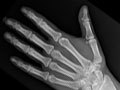

Generalidades de la prueba

Una radiografía de las extremidades es una imagen de la mano, la muñeca, el brazo, el pie, el tobillo, la rodilla o la pierna. Se realiza para ver si se ha fracturado un hueso o si se ha dislocado una articulación. También se usa para ver si hay una lesión o un daño a causa de afecciones, como infección, artritis, crecimientos óseos (tumores) u otras enfermedades de los huesos como osteoporosis.

Una radiografía de las extremidades es una imagen de la mano, la muñeca, el brazo, el pie, el tobillo, la rodilla o la pierna. Se realiza para ver si se ha fracturado un hueso o si se ha dislocado una articulación. También se usa para ver si hay una lesión o un daño a causa de afecciones, como infección, artritis, crecimientos óseos (tumores) u otras enfermedades de los huesos como osteoporosis. En una emergencia, el médico puede observar los resultados iniciales de una radiografía de las extremidades en algunos minutos. En caso contrario, por lo general, un radiólogo tiene listo el informe oficial de la radiografía el día siguiente.